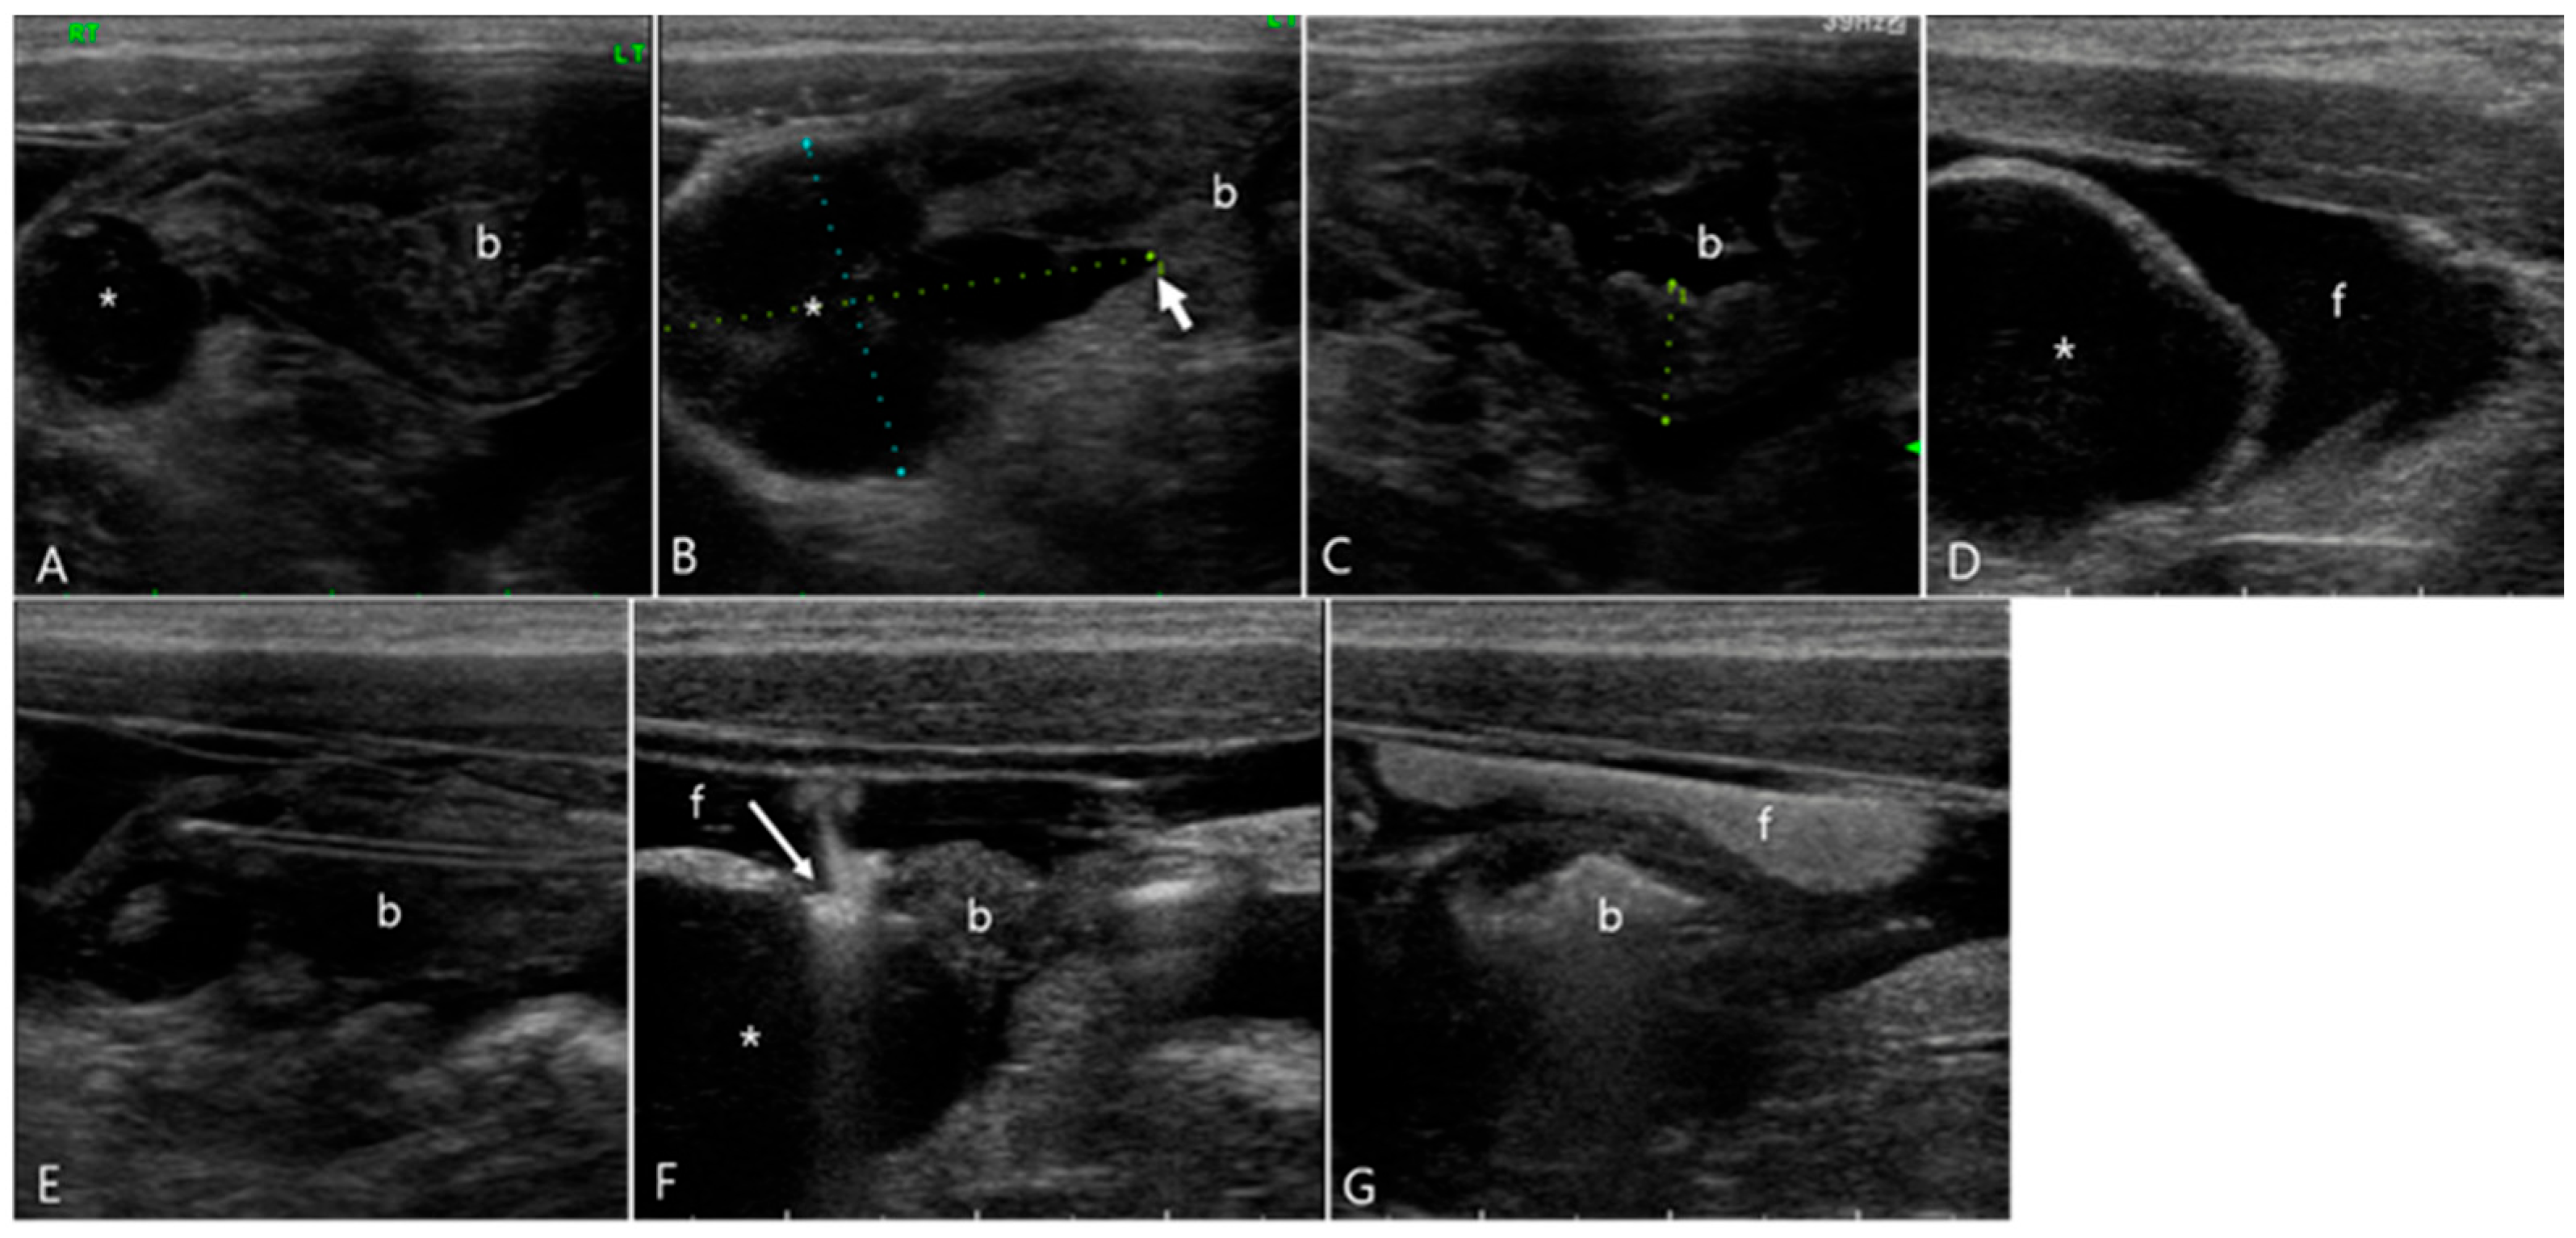

2.1. Case 1

2.2. Case 2

2.3. Case 3

2.4. Case 4

2.5. Case 5

2.6. Case 6